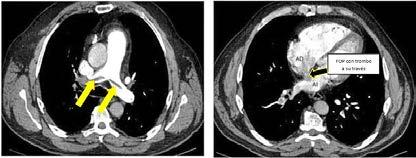

Se realizó una tomografía computarizada (TC) con contraste de forma emergente, que mostró una disección aórtica iatrogénica tipo A focal de origen en la zona 0 del cayado con extensión al tronco braquiocefálico derecho (1) sin afectar al resto de troncos supra-aórticos, cayado o aorta descendente (Figuras 1 y 2); además del hematoma

IATROGÉNICA. ¿QUÉ PUEDE SALIR MAL?

Figuras 1 y 2: Prótesis aórtica migrada y disección aórtica focal tipo A, de origen en la curvatura menor del arco aórtico (zona 0) hasta la bifurcación de la arteria braquiocefálica derecha; sin afectación de del resto de troncos supra-aórticos, del resto del cayado aórtico o de la aorta descendente.